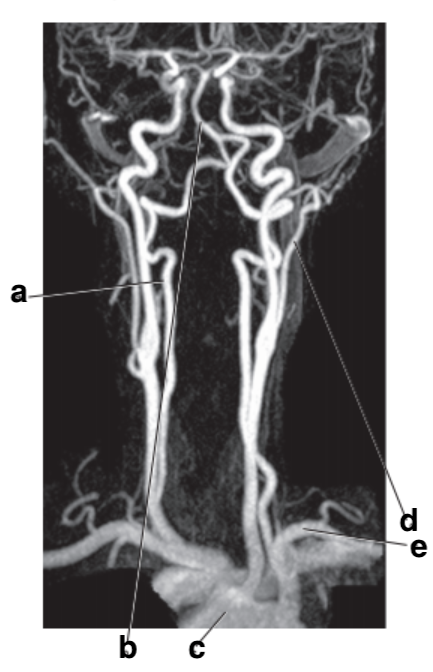

Which letter is the popliteal artery?

A

Which letter is the left common carotid?

left popliteal artery